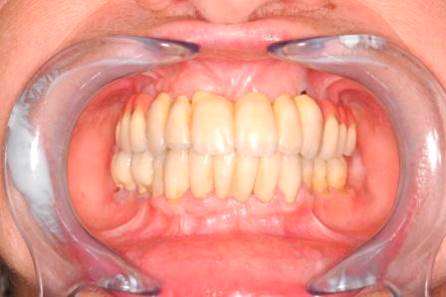

Metoda All-on-four

Bezzubá čelist je hlavní indikací pro ošetření pomocí implantátů. Zejména celkové zubní náhrady v dolní čelisti mají velice nízkou stabilitu a držení díky velkému úbytku kosti.

S pomocí zubních implantátů můžeme díky různým kotevním systémům (třmeny, kulové hlavy, Locatory) zajistit stabilitu a držení protézy nebo při použití většího počtu implantátů zhotovit pevné náhrady – můstky nalepené nebo našroubované na pevno na implantáty.

S těmito typy náhrad můžeme dosáhnout perfektní funkci, výbornou estetiku, fonetiku a současně zajistit u pacienta možnost dobré hygienickou péče a čištění, která je pro životnost implantátů velice důležitá.